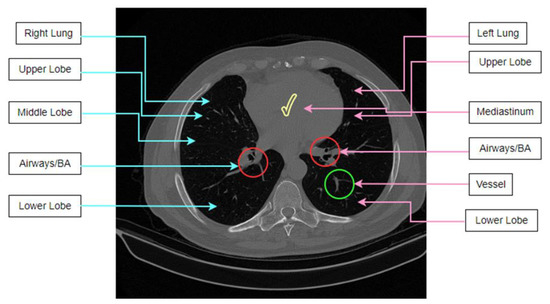

Examples of lung segmentation on various CT scans are presented in Figure 18.

Figure 18. Example outcomes of the lung segmentation process.